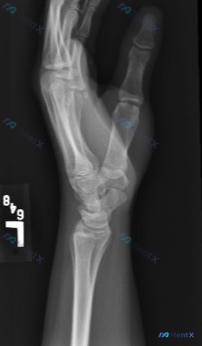

整理到一张左手X光的影像资料,大家可以一起讨论下解读思路: - 影像标记为“L”,是左手的投照 - 但不是标准的正位/侧位/斜位,而是手部处于“OK”手势(拇指与食指捏合)的特殊体位 - 图像清晰度尚可,能看到基本骨性结构 - 当前投照下,各掌骨、指骨骨皮质连续,未见明显骨折线或脱位;关节间隙也没有...